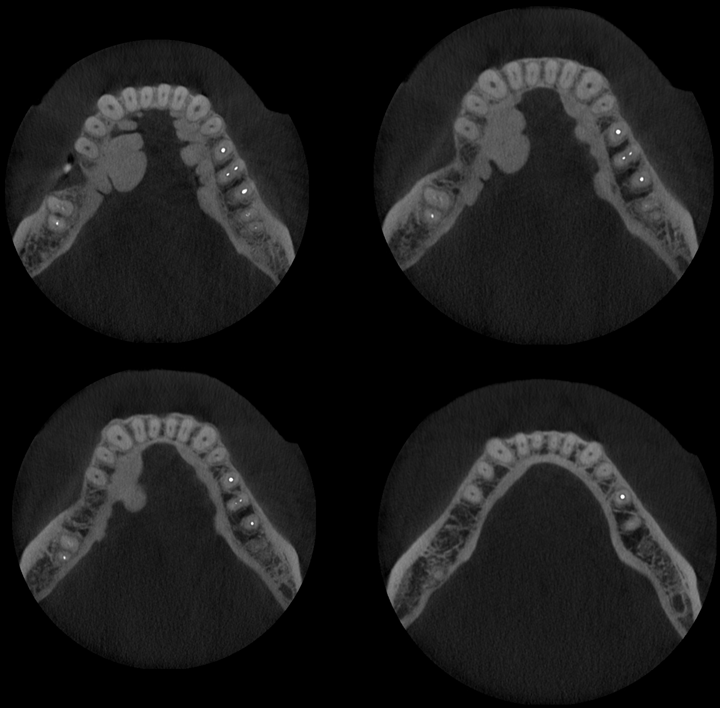

A la evaluación de la tomografía volumétrica (CBCT) en los cortes axiales (Figura 2) y transaxiales (Figura 3), se evidencia múltiples excresencias óseas de forma lobular localizadas hacia lingual a nivel de piezas 36, 35, 34, 44, 45. Características imagenológicas compatible con exostosis óseas (Torus Lingual)

CORTES AXIALES